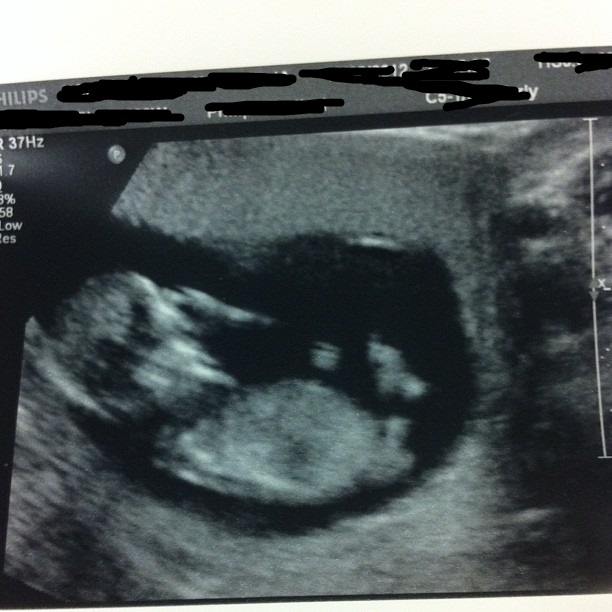

hi heres my 12 week 6 day scan picture .. im not sure if a nub is visible but guesses? Attachment 4114

I say boy also. Not best quality pic.... but top shows a nice classic upwards male nub. I'd still hold out shopping until a better pic can confirm.* I I hesitate only because both legs are not completely obvious in that pic. So possibly what may be a nub may be a blur of a leg... do you see what I mean? Good luck.

If what I think is the nub is the nub then boy but I'd say there is room for error for sure!